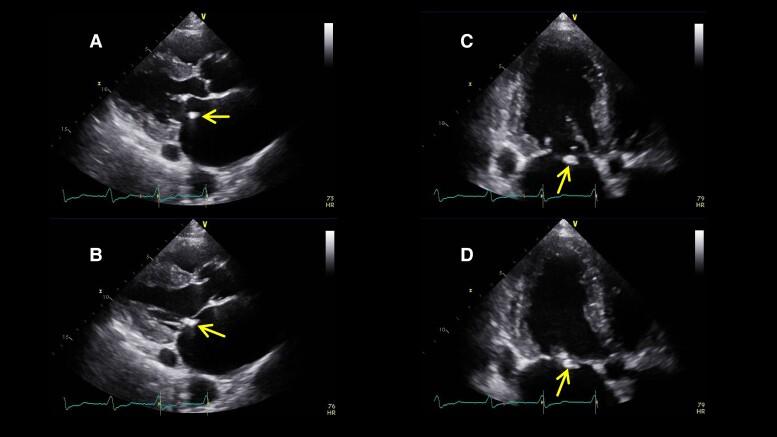

An 89-year-old man underwent mitral valve repair with an annuloplasty ring for moderate atrial functional MR (AFMR). Post-operative transthoracic echocardiography on Day 7 suggested a dislodged mitral annuloplasty ring and recurrent moderate AFMR. However, the MR developed severely, which led to two hospitalizations for congestive heart failure in the past year. Transoesophageal echocardiography (TOE) was performed carefully to ensure that the TEER clip did not interfere with the dislodged annuloplasty ring. Consequently, only the therapeutic target on the medial side of the A2-P2 region was approached posteriorly behind the peri-ring space, without gripper interference.

一名89岁男性因中度心房功能性二尖瓣反流(AFMR)接受二尖瓣瓣环成形术修复。术后第7天经胸超声心动图显示二尖瓣瓣环成形环移位且AFMR复发。然而,二尖瓣反流严重,导致患者在过去一年因充血性心力衰竭住院两次。仔细进行经食管超声心动图(TOE)检查以确保TEER夹不会干扰移位的瓣环成形环。因此,仅在A2-P2区域内侧的治疗靶点在瓣环周围间隙后方经后路处理,未受到夹钳干扰。